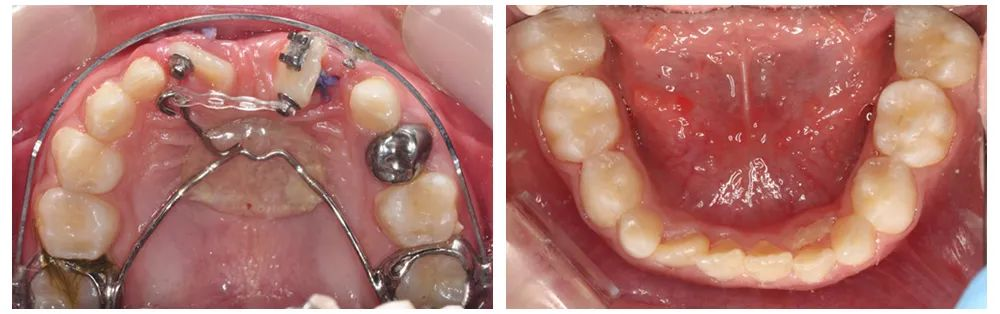

▲术中情况

▲术后情况